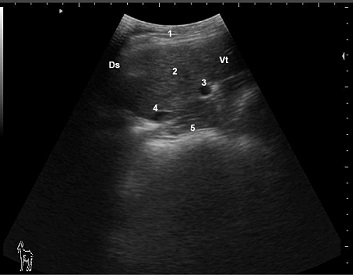

Ultrasonogram of hepatic parenchyma and hepatic blood vessels in a healthy late pregnant doe viewed from the 10th ICS on the right side

1: Lateral abdominal wall; 2: Liver parenchyma; 3: Portalvein; 4: Caudal vena cave; 5: Omasum; Ds: Dorsal; Vt: Ventral